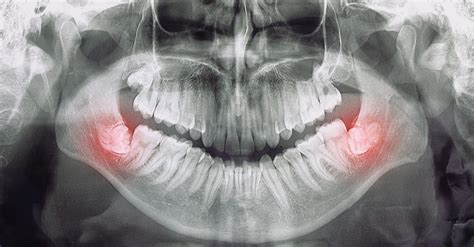

- Cordales retenidos: estos están completamente ocultos dentro de la encía. Las muelas del juicio ocultas pueden causar dolor, producido por infecciones, que dañan las raíces o los huesos de dientes contiguos. Además, pueden generar quistes o tumores de forma excepcional.

- Cordales parcialmente erupcionados: estos emergen de la encía a medias y, debido a la dificultad para mantener la higiene de la zona, se acumulan restos de alimentos y favorece la acumulación de bacterias, pudiendo provocar caries, abscesos de pus en la encía e incluso infecciones.